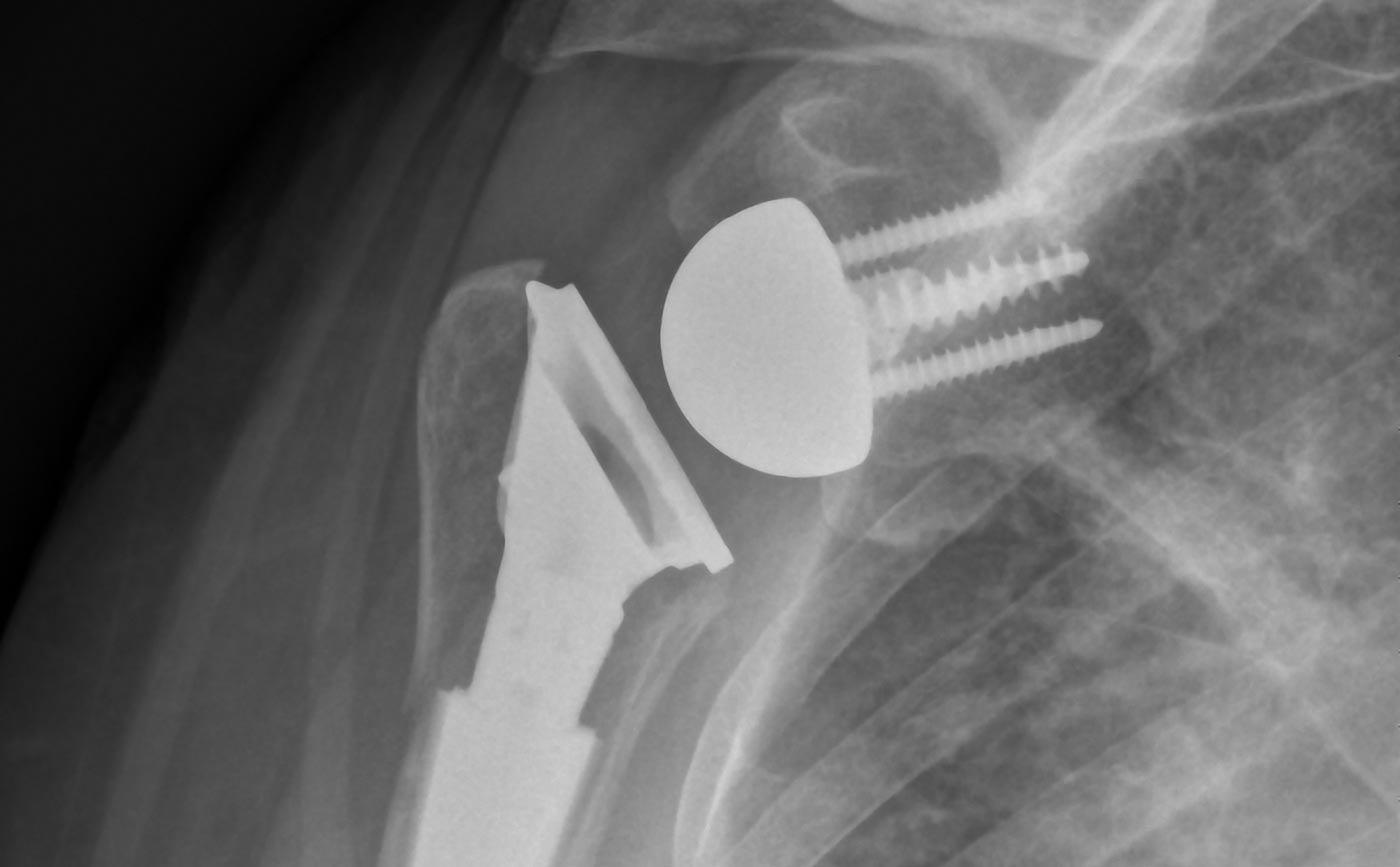

The Catalyst Fracture Shoulder System addresses the unique challenges of managing proximal humeral fractures (PHFs). Unlike traditional reverse for fracture arthroplasty systems, it prioritizes tuberosity fixation and healing – key factors shown to enable improved outcomes – while delivering post-operative stability and surgical efficiency. The patented stem design promotes simplified tuberosity management and allows for uncemented diaphyseal fixation even in the presence of osteoporotic bone.

THE FUTURE OF TUBEROSITY MANAGEMENT IS HERE